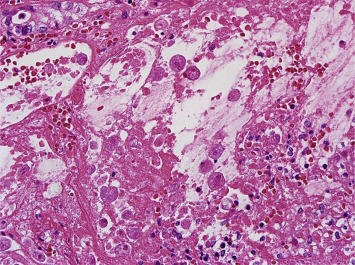

An emergency operation was performed, and multiple perforations from the ascending colon to the rectum, significant pus debris at the peritoneum, and massive dirty ascites were discovered. Amebic trophozoites (Fig. 5), CMV inclusion bodies (Fig. 6), and fungal hyphae (Fig. 7) were identified in the resected colon specimen. Broad-spectrum antibiotics with an antifungal agent were prescribed. Serum tests showed positive IHA for amoeba, and a CMV viral load of 272,000 cp/mL. The ascites culture yielded Enterococcus faecium, Candida albicans, and Candida krusei. The pleural effusion culture yielded Aspergillus fumigatus. Despite aggressive medical treatment, his condition deteriorated gradually, and he passed away about 10 weeks after admission.

Figure 5. Microscopic view of the resected specimen showing amebic trophozoites at the site of the colon ulcers. |